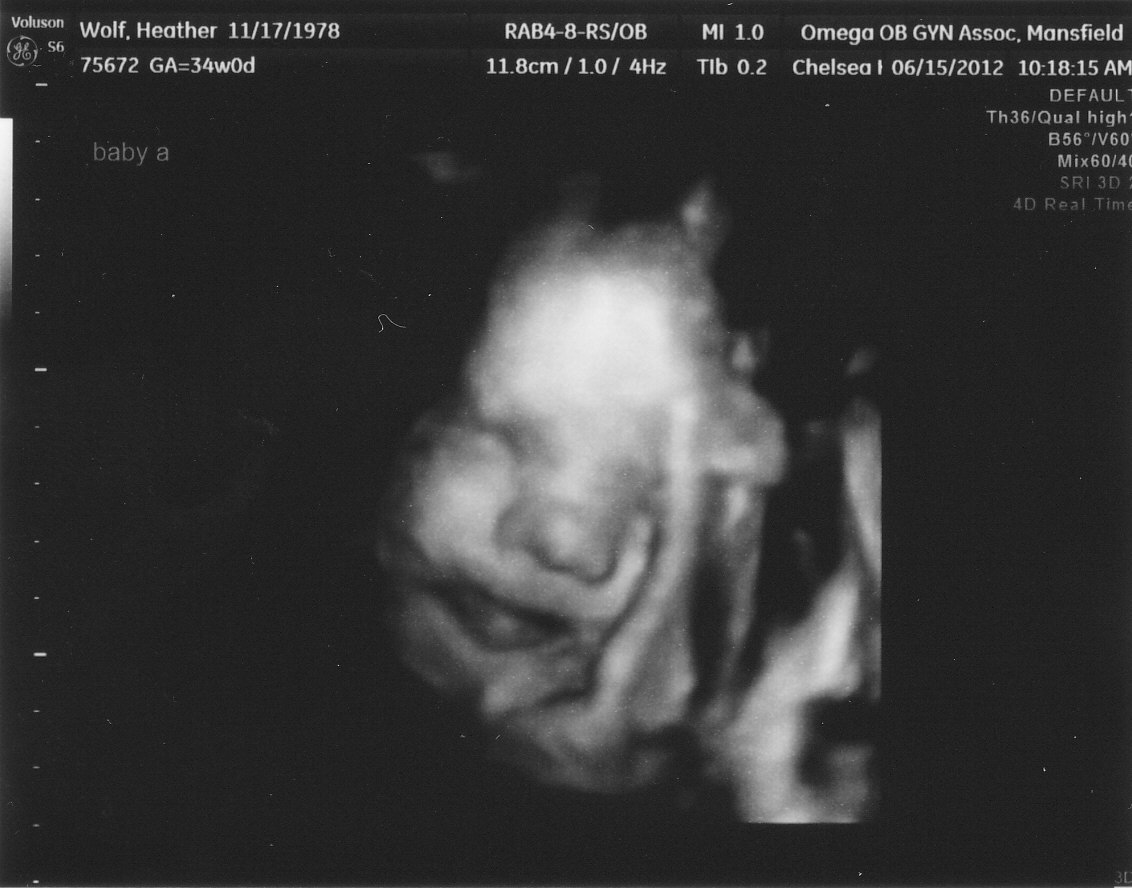

Here is a picture of our Baby Girl. Our Baby Boy was being shy and wouldn't show his face this time . . . little bugger =)

| here she's looking right towards ya and her arm is up by her face (that funny twig looking thing) |